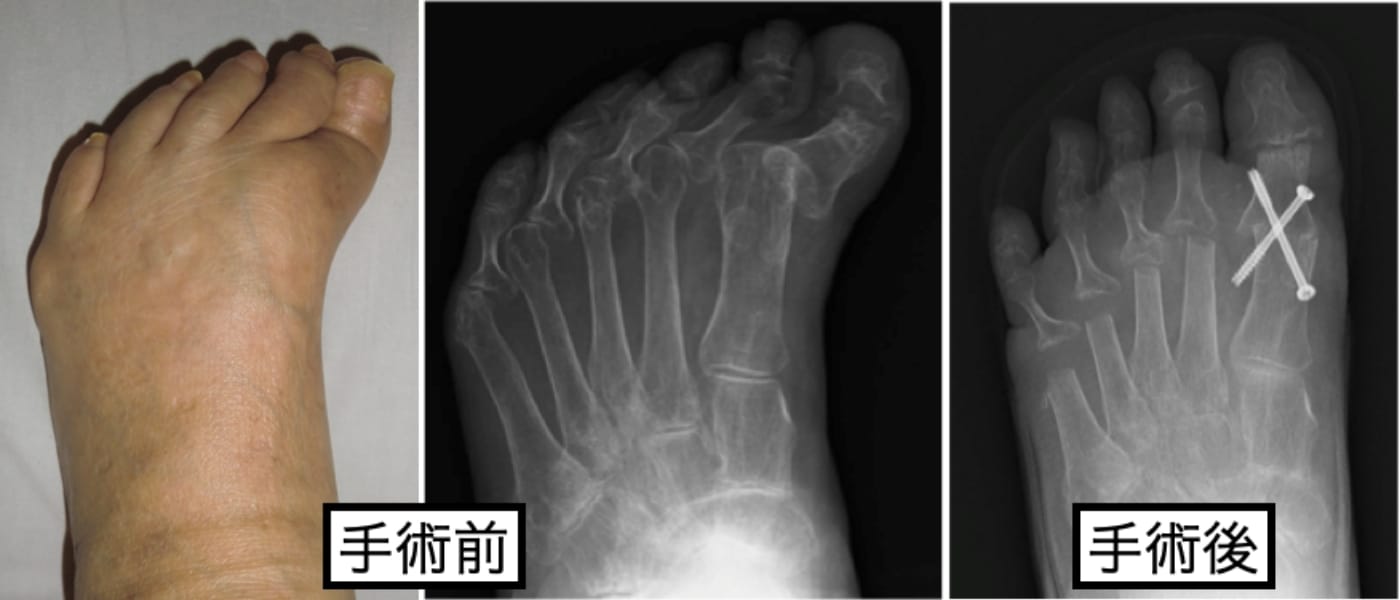

関節リウマチによる足部変形

当科では、関節リウマチによる前足部変形に対して、従来行われていた第1MTP関節固定術と第2〜5中足骨頭切除による切除関節形成術を組み合わせた足趾形成術も行なっております(下図)が

抗リウマチ治療により、疾患活動性が落ち着いている場合や足趾関節の破壊が高度でなければ、可能な限り関節温存型の足趾形成術を行なっています(下図)。

足趾関節を温存することで、足部の踏み返し運動の改善が期待できるため、歩容の改善も期待できます。また、中足骨頭を残す際に骨頭の配列も矯正するため、足底部の有痛性胼胝の自然軽快も期待できます(下図)。